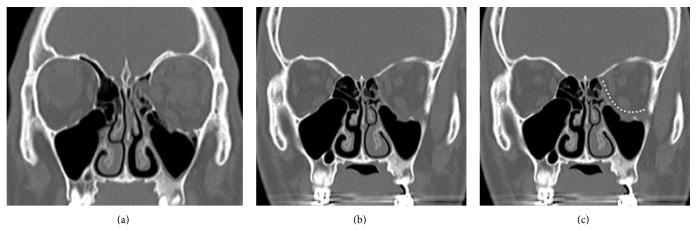

Blowout fracture characterized by concurrent floor and medial wall fractures is a rare entity. We compared surgical outcomes between a single approach and a double approach in patients with orbital fracture by measuring the postoperative orbital volume.

We confirmed that 21 (8.5%) of a total of 246 patients with orbital fractures had fractures of the medial wall and floor through a retrospective chart review. Of these, 10 patients underwent the single approach and the remaining 11 patients had the double approach. We performed a statistical analysis of changes between the preoperative and postoperative orbital volumes at a 6-month follow-up.

Compared with the contralateral, nonaffected side, the orbital volume was 115.3 (±6.09)% preoperatively and 106.5 (±6.15)% postoperatively in the single approach group and 118.2 (±11.16)% preoperatively and 108.6 (±13.96)% postoperatively in the double approach. These results indicated that there was a significant difference between the preoperative and postoperative orbital volumes in each group (P < 0.05). However there was no significant difference between the single approach and the double approach (P > 0.05).

Our results showed that there were no significant differences in surgical outcomes between the two modalities. The treatment modality may be selected based on the surgeons' preference, as well as the fracture type.